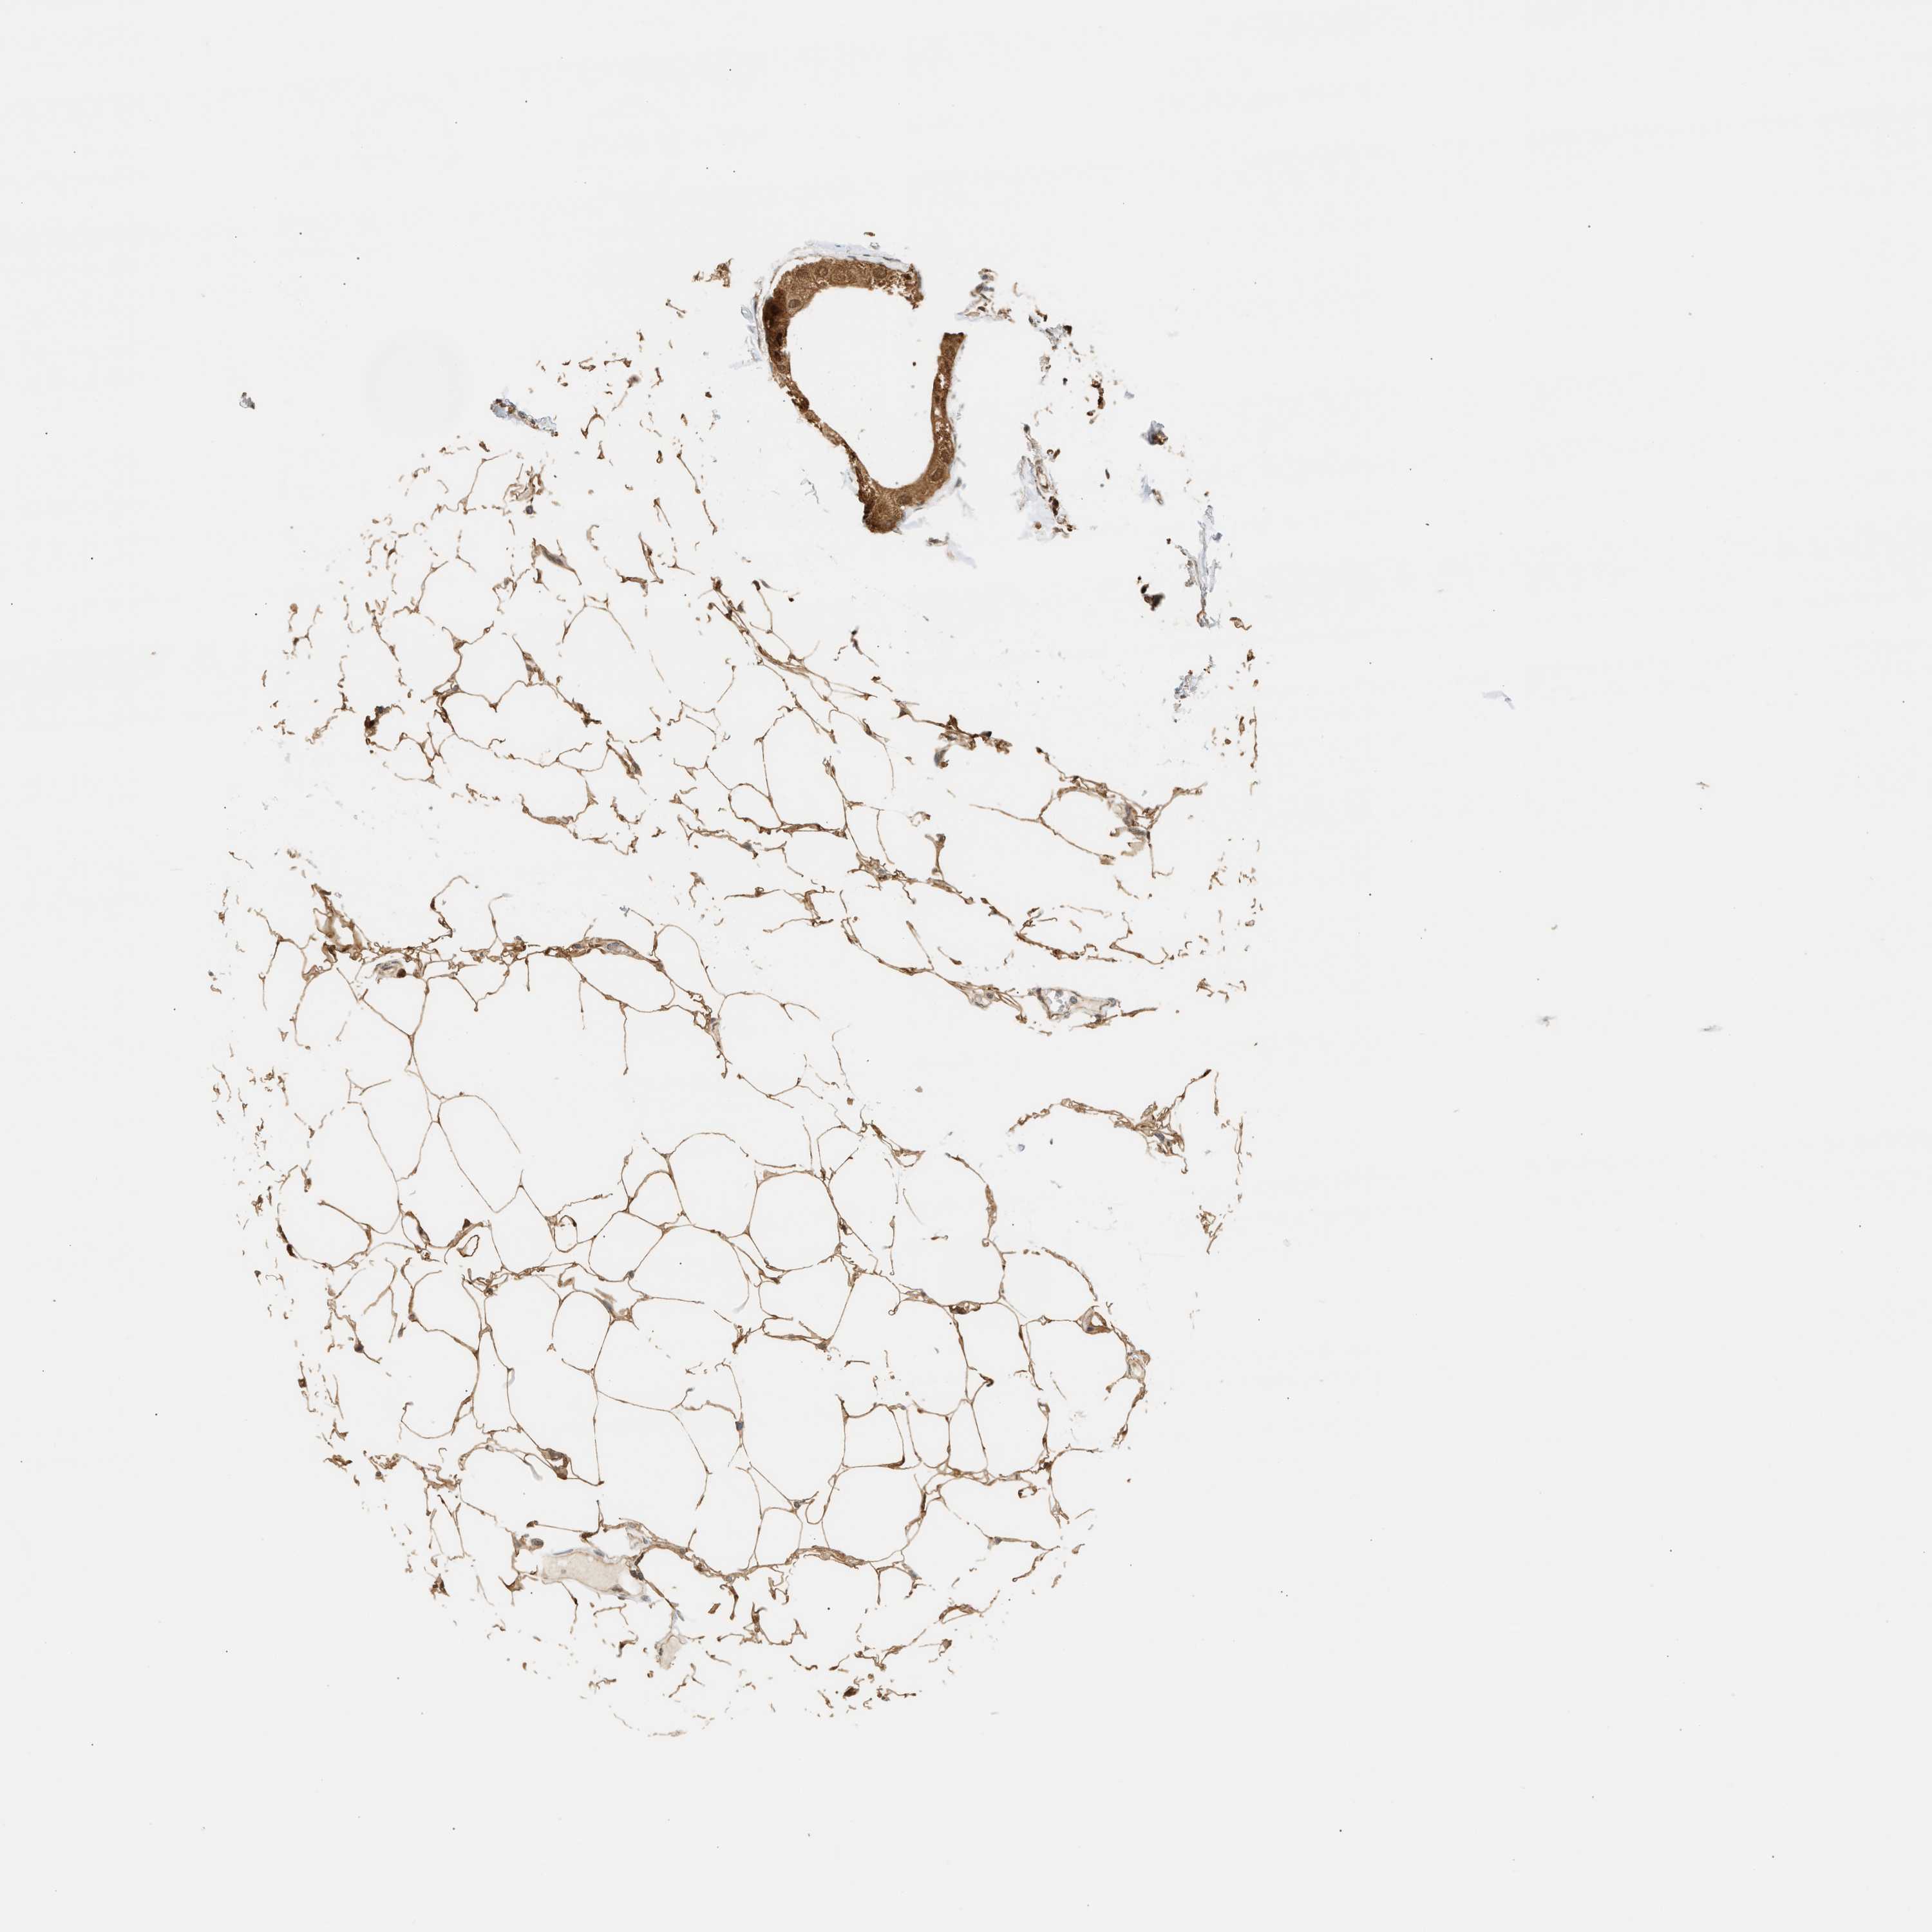

BRCA TCGA BRCA VALIDATION PROTEIN EXPRESSION

Breast cancer

Human cancer